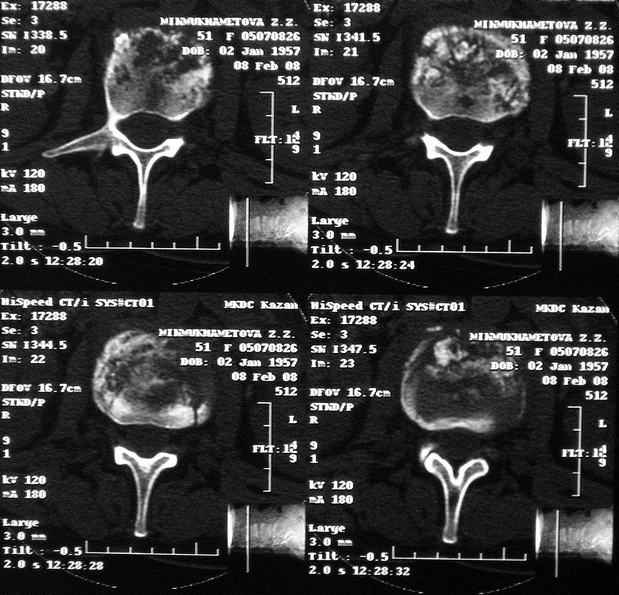

Re: Требуется телеконсультация Вертебролога

MRI через три недели